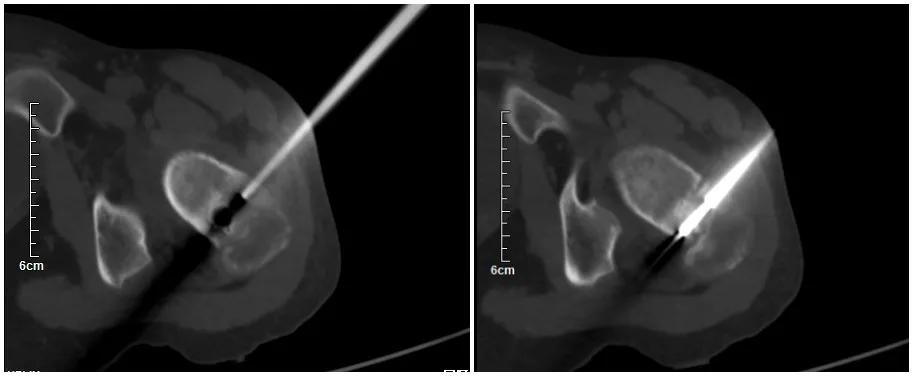

近日,我科在华西医院段宏教授指导下成功完成国内首例AR辅助股骨颈肿瘤精准治疗手术。手术时间短,精准定位,更好地减少失血和软组织损害以及术后疼痛。

我院术前图片

由于邓某某年龄较小,骨骺未愈合,手术难度大,如若进行切开手术治疗,手术创伤较大,还不一定能找到肿瘤。同时,邓某某左侧股骨颈肿瘤位置距离骨骺线较近,若不能精准定位,极易破坏骨骺线,导致患肢停止生长。对于肿瘤侵犯左侧股骨颈,肿瘤继续生长危害极大,肿瘤切除仍然是治疗的关键。考虑到患者的实际情况,与家属沟通后,在华西段宏教授指导下我科为患者成功进行了国内首例AR辅助股骨颈肿瘤精准治疗手术。

AR技术是把患者医学影像重建后的虚拟模型与真实世界相融合,运用光学显示技术、人机交互技术、位置坐标跟踪、标定、注册等前沿科学技术,为使用者提供一个全方位、多角度、沉浸式、可交互的操作体验。并且可以将虚拟信息与现实场景信息进行对位匹配,在手术中可以精准定位病灶位置,为医生提供更轻松、迅速和安全地手术辅助形式,对患者来说,可以大大减小手术对患者的伤害。